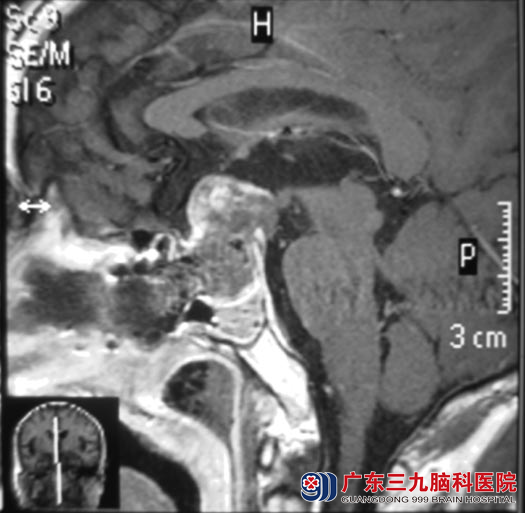

5月28日,由鲁明主任主刀,根据导航计划行经鼻碟入路鞍去肿瘤切除手术,术中显微镜下进入蝶窦后,再次导航定位肿瘤位置,磨开鞍底后见肿瘤组织,呈灰白色,胶状,予肿瘤切除。术后视力、视野基本恢复正常,未出现脑脊液漏、尿崩等术后并发症。术后病理结果为:垂体促性腺激素分泌腺瘤并卒中。

▲手术后